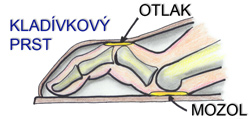

Kladívkový prst patří mezi časté deformity prstů dolních končetin, kdy se deformují klouby porušením rovnováhy mezi krátkými a dlouhými svaly nohy. Jsou to jakési skrčeniny prstoů. Postižení se objevuje se stoupajícím věkem a vzniká hlavně na 2. prstu, nicméně může vzniknout na kterýmkoliv prstu kromě palce. Prst se postupně ohýbá, nelze ho narovnat a tlakem obuvi se na vrcholku prvního článku vytvoří otlak, i bolestivé kuří oko.

Pokud je prst ohnutý již ve vašech kloubech, jde o deformitu nazývanou drápový prst.